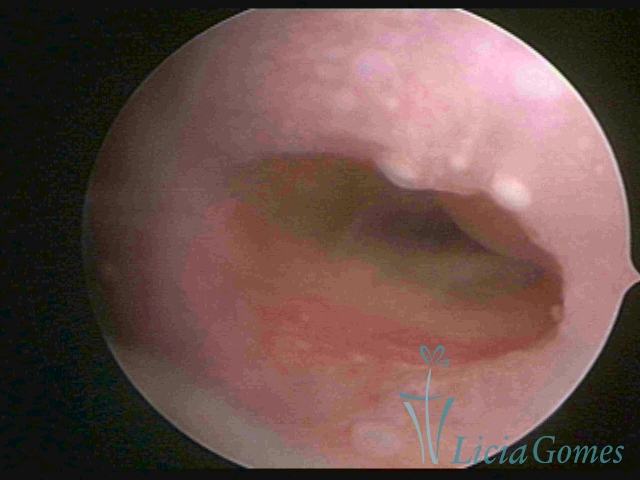

Second part or middle section

In the middle section of the cervical canal, the details of the buds are lost. It is possible to view creases and crypts. Longitudinal grooves are frequently observed. They are the most compact tissues presenting the most vascularized surface, whose vessels follow its passageway.